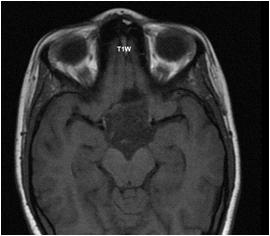

Fig 1 — Axial CT scan of brain at the level of posterior fossa demonstrates an area of high attenuation in the right cerebellum which denotes acute hematoma.(white arrow) Also note the effacement of the adjacent fourth ventricle and compression of the brainstem.